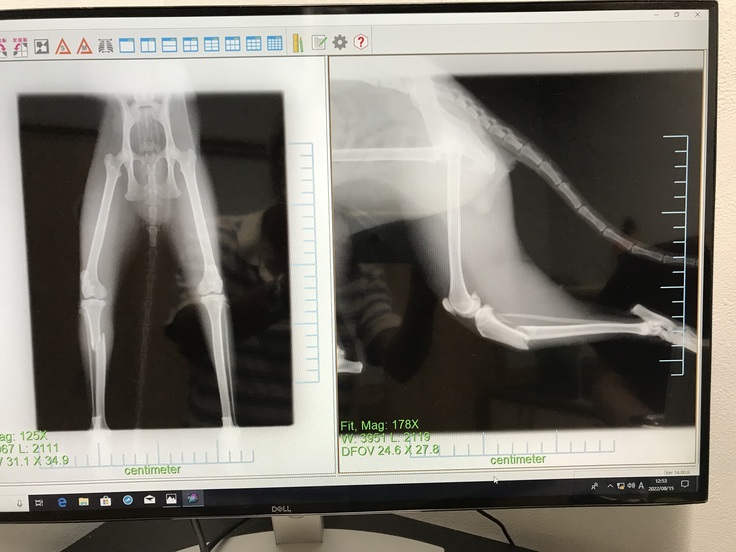

翌日、動物病院でレントゲンを撮影すると、右足の膝下を骨折していました。

8月20日に手術を受けました。

手術は、上手くいきましたが、骨がなかなか繋がらなくて、チビが動いてしまうために骨を固定しているプレートがズレて、再手術を受けました。

骨は何とか微妙につながりましたが、手術跡の皮膚が再生しませんでした。

骨がなかなか繋がらなくて2回の手術をうけましたが、真っ直ぐに上手くつながりませんでした。

ビッコになりましたがヨタヨタ歩いています。まだ走ってるところは見たことがありません。

これから少しづつリハビリ運動して筋肉がついてくれば、上手く歩けて、走れるようになってくれると思います。